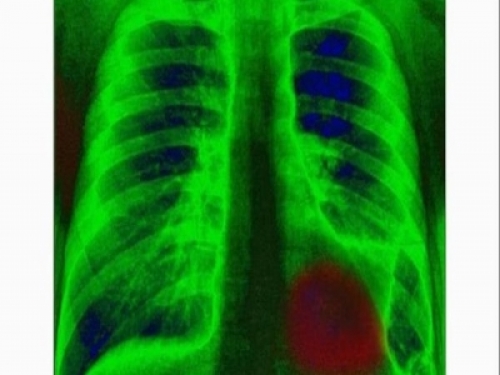

肺癌患者的飲食要注意啥?肺癌是目前世界上發病率比較高的一類疾病,它的死亡率也比較高。患者朋友一經發現就需要積極的治療。並且在治療的同時在飲食方法也需要注意,那麼肺癌患者的飲食要注意啥呢?一起看看吧。

肺癌患者的飲食要注意啥?